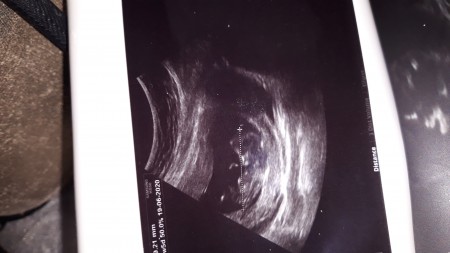

arkadaşlar 12 haftalık tahmini olan varmi dr um 2 hafta sonra dedi söylemek için ama heyecandan sizlere sormak istedim şimdiden tesekkurler

Gebelik haftası 12 hafta

Kız gibi geldi bana Rabbim hayırlısını versin inşallah amin<3